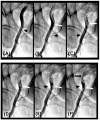

Background: In the study of coronary artery disease, the mechanisms underlying atherosclerosis initiation and progression or regression remain incompletely understood. Our research conceptualized the cardiovascular system as an integrated network of pumps and pipes, advocating for a paradigm shift from static imaging of coronary stenosis to dynamic assessments of coronary flow. Further review of fluid mechanics highlighted the water hammer phenomenon as a compelling analog for processes in coronary arteries. Methods: In this review, the analytical methodology employed a comprehensive, multifaceted approach that incorporated a review of fluid mechanics principles, in vitro acoustic experimentation, frame-by-frame visual angiographic assessments of in vivo coronary flow, and an artificial intelligence (AI) protocol designed to analyze the water hammer phenomenon within an acoustic framework. In the analysis of coronary flow, the angiograms were selected from patients with unstable angina if they had previously undergone one or more coronary angiograms, allowing for a longitudinal comparison of dynamic flow and phenomena. Results: The acoustic investigations pinpointed pockets of contrast concentrations, which might correspond to compression and rarefaction zones. Compression antinodes were correlated to severe stenosis, due to rapid shifts from low-pressure diastolic flow to high-pressure systolic surges, resulting in intimal injury. Rarefaction antinodes were correlated with milder lesions, due to de-escalating transitions from high systolic pressure to lower diastolic pressure. The areas of nodes remained without lesions. Based on the locations of antinodes and nodes, a coronary acoustic action map was constructed, enabling the identification of existing lesions, forecasting the progression of current lesions, and predicting the development of future lesions. Conclusions: The results suggested that intimal injury was likely induced by acoustic retrograde pressure waves from the water hammer phenomenon and developed new lesions at specifically exact locations.